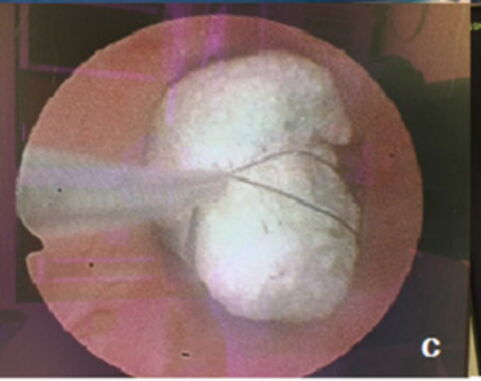

According to MailOnline, doctors managed to remove the 4-inch-long foam that was lodged in his bladder, but the procedure on his penis turned out to be more complicated. They eventually had to cut out a new opening in between his scrotum and anus, making it possible for him to urinate.